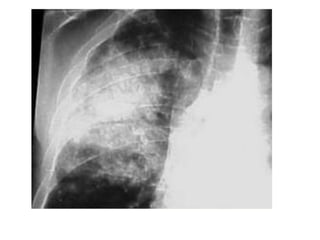

• #51 Paciente masculino de 63 años que refiere tos, disnea y dolor torácico derecho de aproximadamente siete días de evolución. El examen físico revela hipo ventilación en hemitorax derecho. Como dato positivo de laboratorio presenta VSG aumentada. Se solicita inicialmente una radiografía de tórax frente en la cual se observa, radioopacidad basal derecha con broncograma aéreo que borra el seno costofrénico homolateral. Engrosamiento pleural difuso que impresiona comprometer pleura mediastínica. Dados los hallazgos en la radiografía se decide ampliar el diagnostico solicitándole una TAC de tórax con contraste endovenoso en la cual se observa engrosamiento circunferencial pleural de hemitorax derecho. Atelectasia de segmentos inferiores con broncograma aéreo. Pequeña área líquida tabicada. Adenomegalias mediastinales en región prevascular, pretraqueal retrocavo y ventana aortopulmonar. Caja torácica sin alteraciones tomográficamente demostrables. Estructura y densitometría osteoarticular de l raquis dorsal normal. DIAGNOSTICOS DIFERENCIALES: • Engrosamiento pleural: Derrame organizado, hemotórax, piotorax, cirugía previa, radioterapia, exposición al Asbesto. • Tumores Benignos: lipomas, tumores fibrosos, esplenosis torácica. • Tumores malignos: MTTS de pulmón, mama, linfoma. • Mesotelioma maligno. DIAGNOSTICO DEFINITIVO: • MESOTELIOMA MALIGO